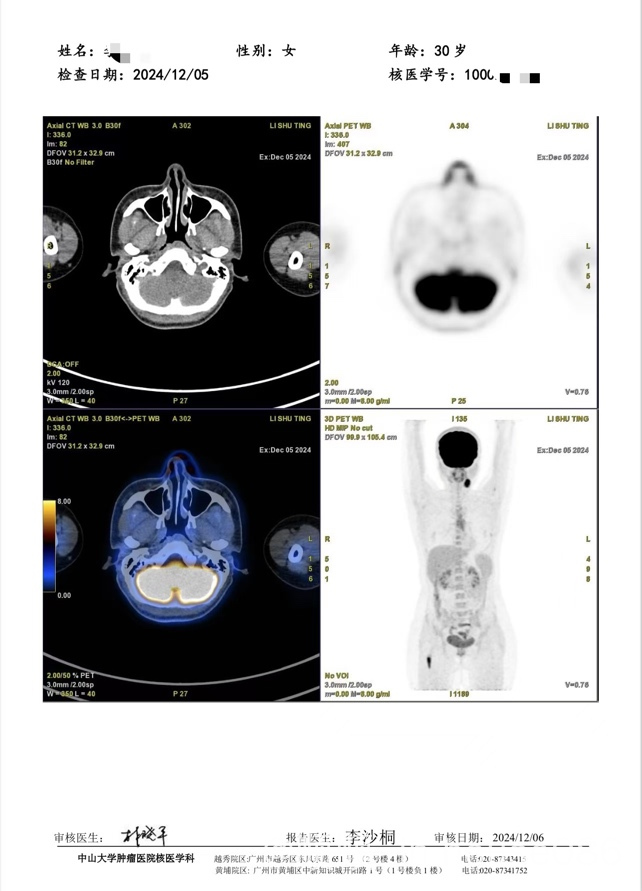

- 滤泡性淋巴瘤1-2级

一般来说,与转化性滤泡性淋巴瘤最相关的基因突变有三个,分别是MYC,B2M和CDKN2A/B,从这份NGS报告来看,有B2M和CDKN2A两个突变,考虑发生转化的可能性大,需要做化疗,三个疗程的R-CHOP加放疗巩固。 |